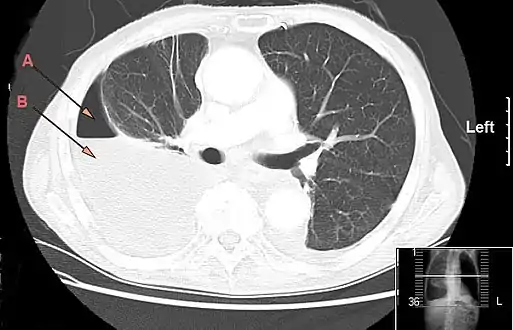

CT chest showing large right sided hydro-pneumothorax from pleural empyema. Arrows A: air, B: fluid

The initial investigations for suspected empyema remains chest X-ray, although it cannot differentiate an empyema from uninfected parapneumonic effusion.[5] Ultrasound must be used to confirm the presence of a pleural fluid collection and can be used to estimate the size of the effusion, differentiate between free and loculated pleural fluid and guide thoracocentesis if necessary. Chest CT and MRI do not provide additional information in most cases and should therefore not be performed routinely.[6] On a CT scan, empyema fluid most often has a radiodensity of about 0-20 Hounsfield units (HU),[7] but gets over 30 HU when becoming more thickened with time.[8]